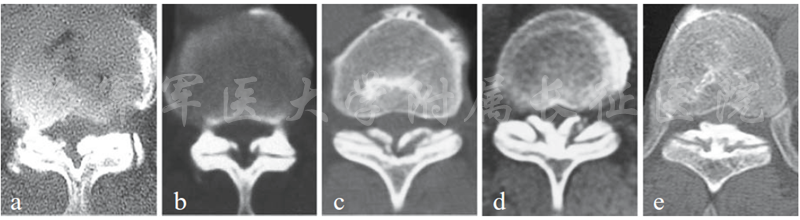

1920年Polar教授通过X线第一次诊断并命名了胸椎黄韧带,之后,胸椎黄韧带逐渐成为胸椎脊髓压迫的主要原因之一[1]。同后纵韧带骨化一样,胸椎黄韧带骨化主要发生在亚洲人群。据报道,日本整体发病率约36%,亚洲南部地区发病率为3.8%[2-4]。从解剖学角度看,胸椎黄韧带主要由内侧的椎板部分和两侧的囊部分组成。通常情况下骨化开始形成于囊部分,然后逐渐向中间和腹侧发展。最后双边骨化的黄韧带在椎板中部融合增厚形成巨大块状骨化物。因此根据CT上骨化黄韧带发展的过程,Sato T等将骨化黄韧带分为五种类型[5](图1):

1.侧块型:骨化仅局限于黄韧带囊性部分;

2.延伸性:骨化向韧带中间部发展,但仍然较薄;

3.扩大型:骨化物宽度与延伸型相似,但是厚度增加,造成椎管后正中部狭窄;

4.融合型:骨化位置类似扩大型,但是双边骨化病变在中部融合;

5.结节型:双边骨化块在中间融合增厚,呈结节状凸向椎管。

图1胸椎黄韧带骨化的影像学分型 a 侧块型;b 延伸型;c 扩大型;d 融合型;e 结节型 (摘自《Ossification of posterior longitudinal ligament》,第二版, K. Yonenobu;K. Nakamara等)